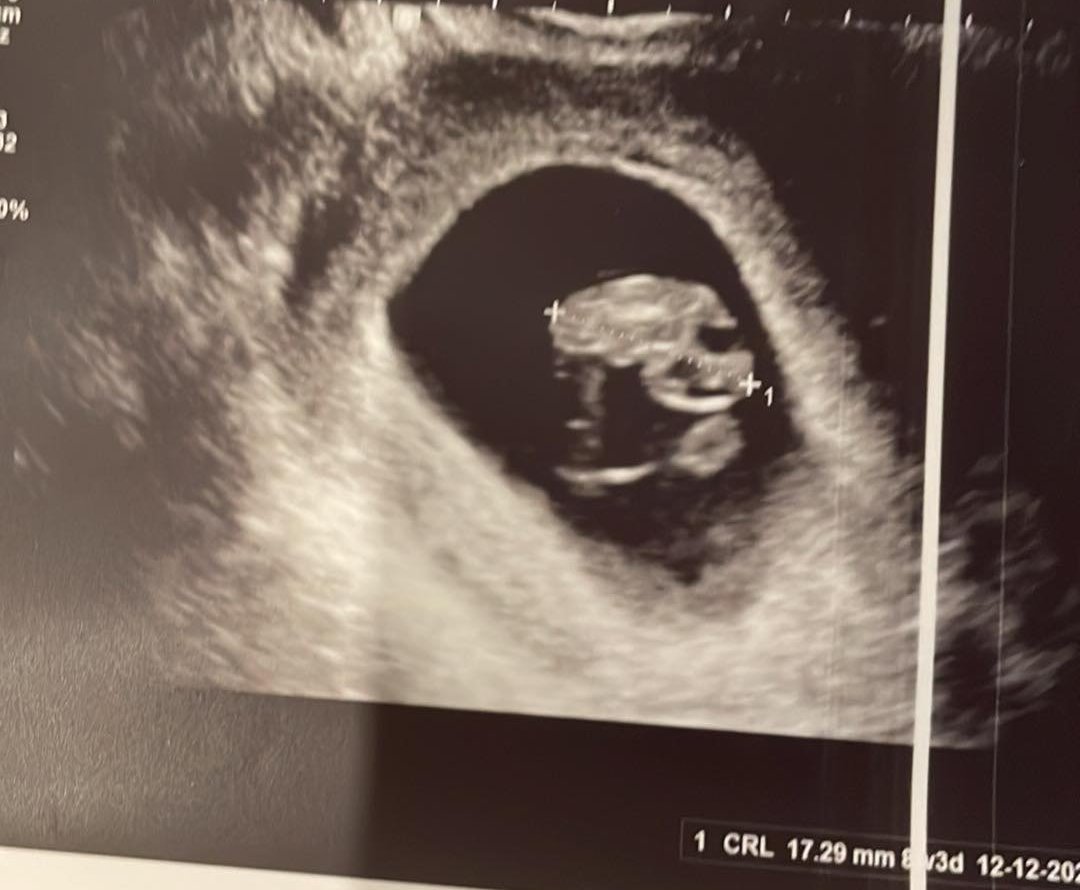

Имам леки притеснения относно кървенето по време на бременност. Някой имал ли е същия проблем и означава ли това спонтанен аборт?

Кървенето по време на бременност може да бъде причинено от различни фактори и не винаги означава спонтанен аборт. Някои жени са имали кървене, но са запазили бременността си. Важно е да се консултирате с вашия лекар и да споделите всички симптоми и притеснения, за да получите професионален медицински съвет.